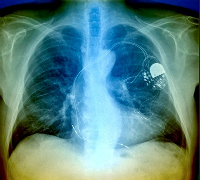

Philippe Mabo és munkacsoportja Franciaország 43 szívsebészeti központjában 538 beteg szinuszcsomó tünetcsoportban szenvedő beteget gyűjtött össze. Valamennyien azonos típusú pacemakert kaptak, de azt követően a teljes csoportot véletlenszerűen két részre osztották.

A következő 18 hónapban 269 beteg az eddig kidolgozott módszer szerint meghatározott időben megjelent ellenőrző vizsgálatra és azt a szívgyógyászati központ munkatársai előírásosan elvégezték. A másik ugyanolyan létszámú csoport nem látogatta meg a klinikát, mert a pacemakerében lévő műszer sűrűn, éjjel-nappal jeleket sugárzott a gyártó cég központjába és a bármilyen kezelést igénylő ritmuszavart számítógépen a kezelőorvosnak küldött át.

Az elektronikus távellenőrzés betegnek-orvosnak egyaránt időnyereséget jelentett. A pacemaker viselőjét a műszer védte az esetleges ritmuszavar ellen és csak akkor kellett fölkeresnie a klinikát, ha a műszer olyan eltérést mutatott, amely speciális beavatkozást igényelt. A megfigyelési idő alatt a hagyományos módon ellenőrzött csoport tagjai 145 napon jelentek meg a kórházban, míg a távellenőrizettek csupán 28 alkalommal jártak személyesen az intézetben – olvasható a European Heart Journal szaklapban.

Mabo professzor hangsúlyozta, hogy az Egyesült Államokban ez a technika már törvényesen engedélyezett, alternatív módszer. Fontos lenne, hogy ezt az Európai Unióban is szabályozzák és ezzel betegnek és orvosnak egyaránt megkönnyítsék a műszer ellenőrzését.